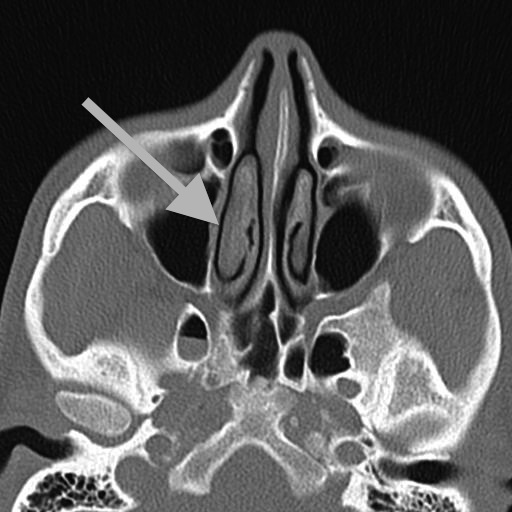

Seen laterally here, my septum used to deviate to the left (remember the sides are switched because it is as if you were looking up at the slice from below).

Seen here from the front, part of my septum hooked out in a way that likely inflamed the abutting turbinate:

The deviated septum was a problem in part because of its interaction with the turbinates, which, when inflamed, block air flow, thereby restricting my breathing. As the CT images show clearly, my turbinates were quite asymmetrical with the right inferior turbinate being significantly larger than its counterpart.

Seen in the lateral slice above:

And a different slice from the front: